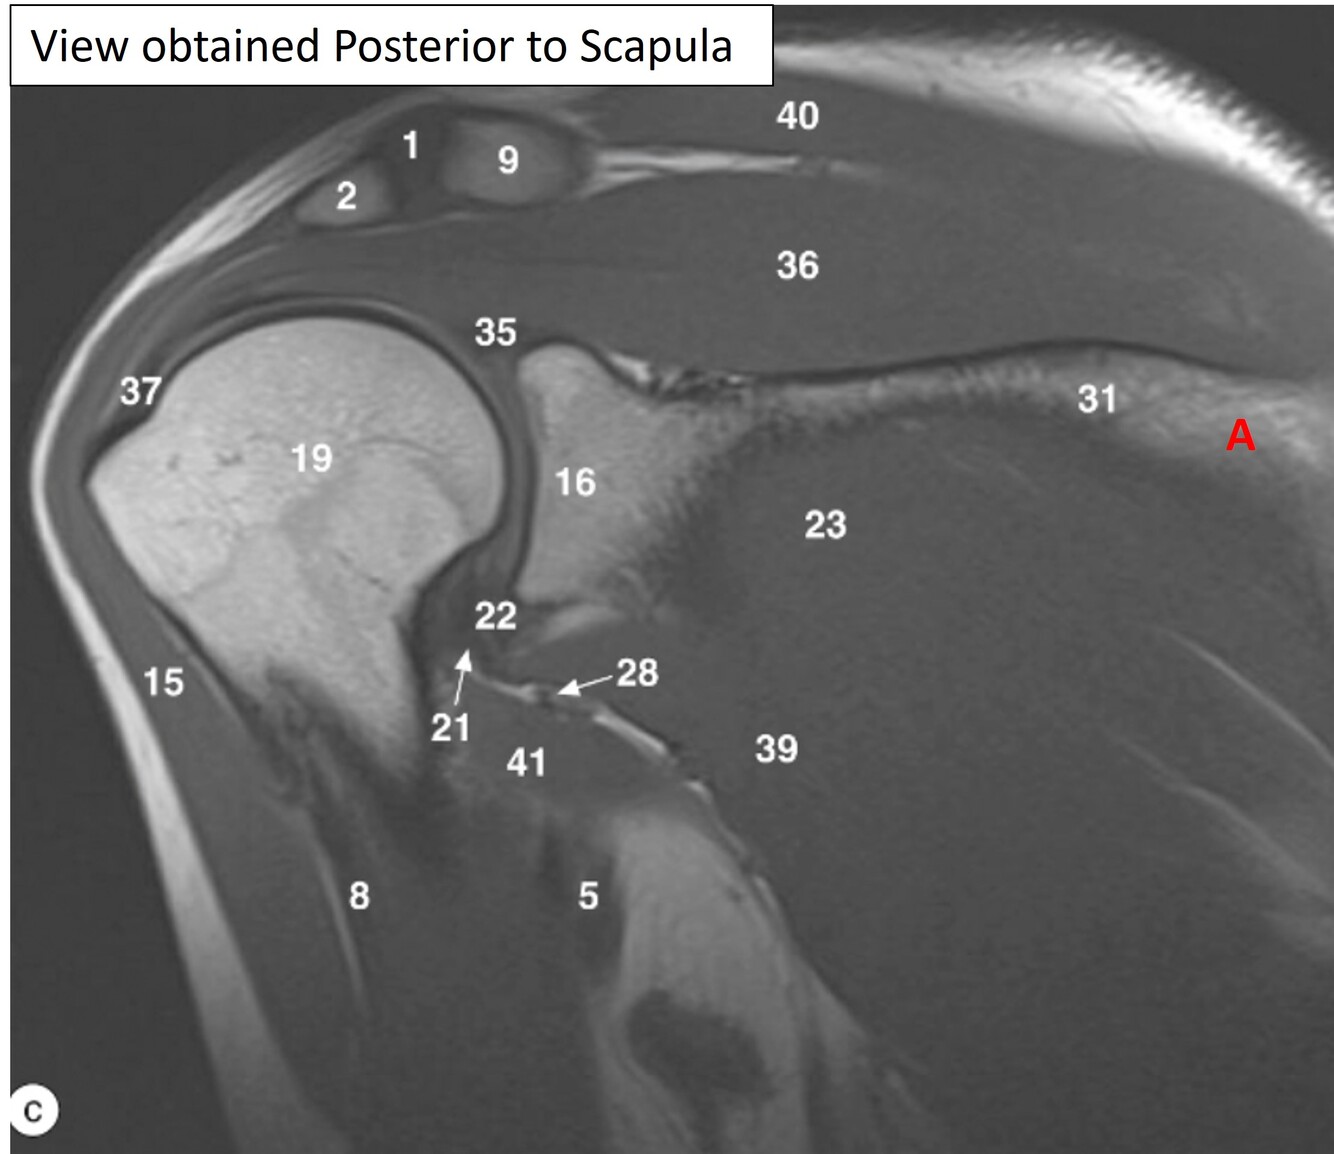

Q

Label 1,2,9,15,36,40

A

1=Rt. AC joint

2=Rt. Acromion of scapula

9=Rt. Clavicle (acromial end)

15=Rt. deltoid muscle

36-Rt. supraspinatous muscle

40=Rt. trapezius muscle

Label 31,13,15,36

31=Spine of rt. scapula

13=Coracoid process of right scapula

36=Rt. supraspinatus muscle

Label 16,18,19,23

16=Glenoid process of Rt. scapula

18=Greater tubercle of Rt. humerus

19=Head of rt. humerus

23=Rt. infraspinatus muscle

4

Label 13,15,16,18,19,23,32

13=Rt. coracoid process

23= Rt. infraspinatus muscle

32=Rt. subscapularis muscle

5

Label 1,2,9,15,16,19

2=Acromion of rt. scapula

6

Label 23, 31,36,39,40

36-Rt. supraspinatus muscle

39=Rt. teres minor

7

Label a

Supraspinous fossa